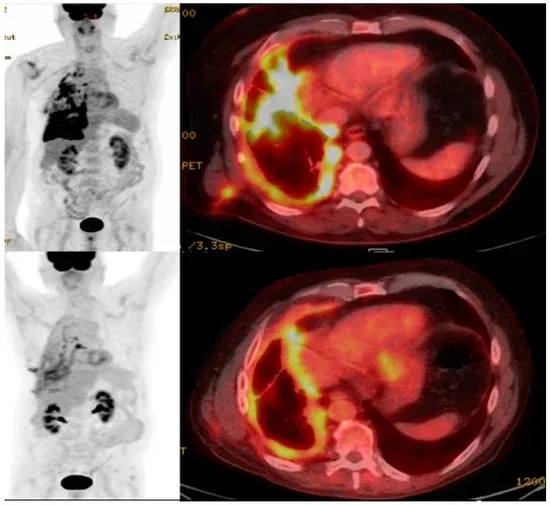

除此之外,既往还报道过一则CAR-T疗法治疗肺癌的振奋案例:一名68岁男性非小细胞肺癌患者,治疗前右侧胸膜存在高摄取转移灶;在接受包含CAR-T细胞疗法的全身治疗后,PET/CT检查显示转移灶高摄取信号明显缩小,直接印证治疗有效。

▲图源“MDPI”,版权归原作者所有,如无意中侵犯了知识产权,请联系我们删除

值得一提的是,下图展示了接受25×10⁶个CAR-T细胞治疗的患者1,在基线和治疗后的正电子发射断层扫描(PET)图像(详见下图B)。

▲图源“N Engl J Med”,版权归原作者所有,如无意中侵犯了知识产权,请联系我们删除